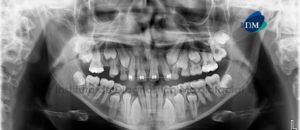

Paciente masculino de 16 años de edad es referido al Instituto de Diagnóstico Maxilofacial (IDM) para su evaluación y diagnóstico. A la evaluación de la